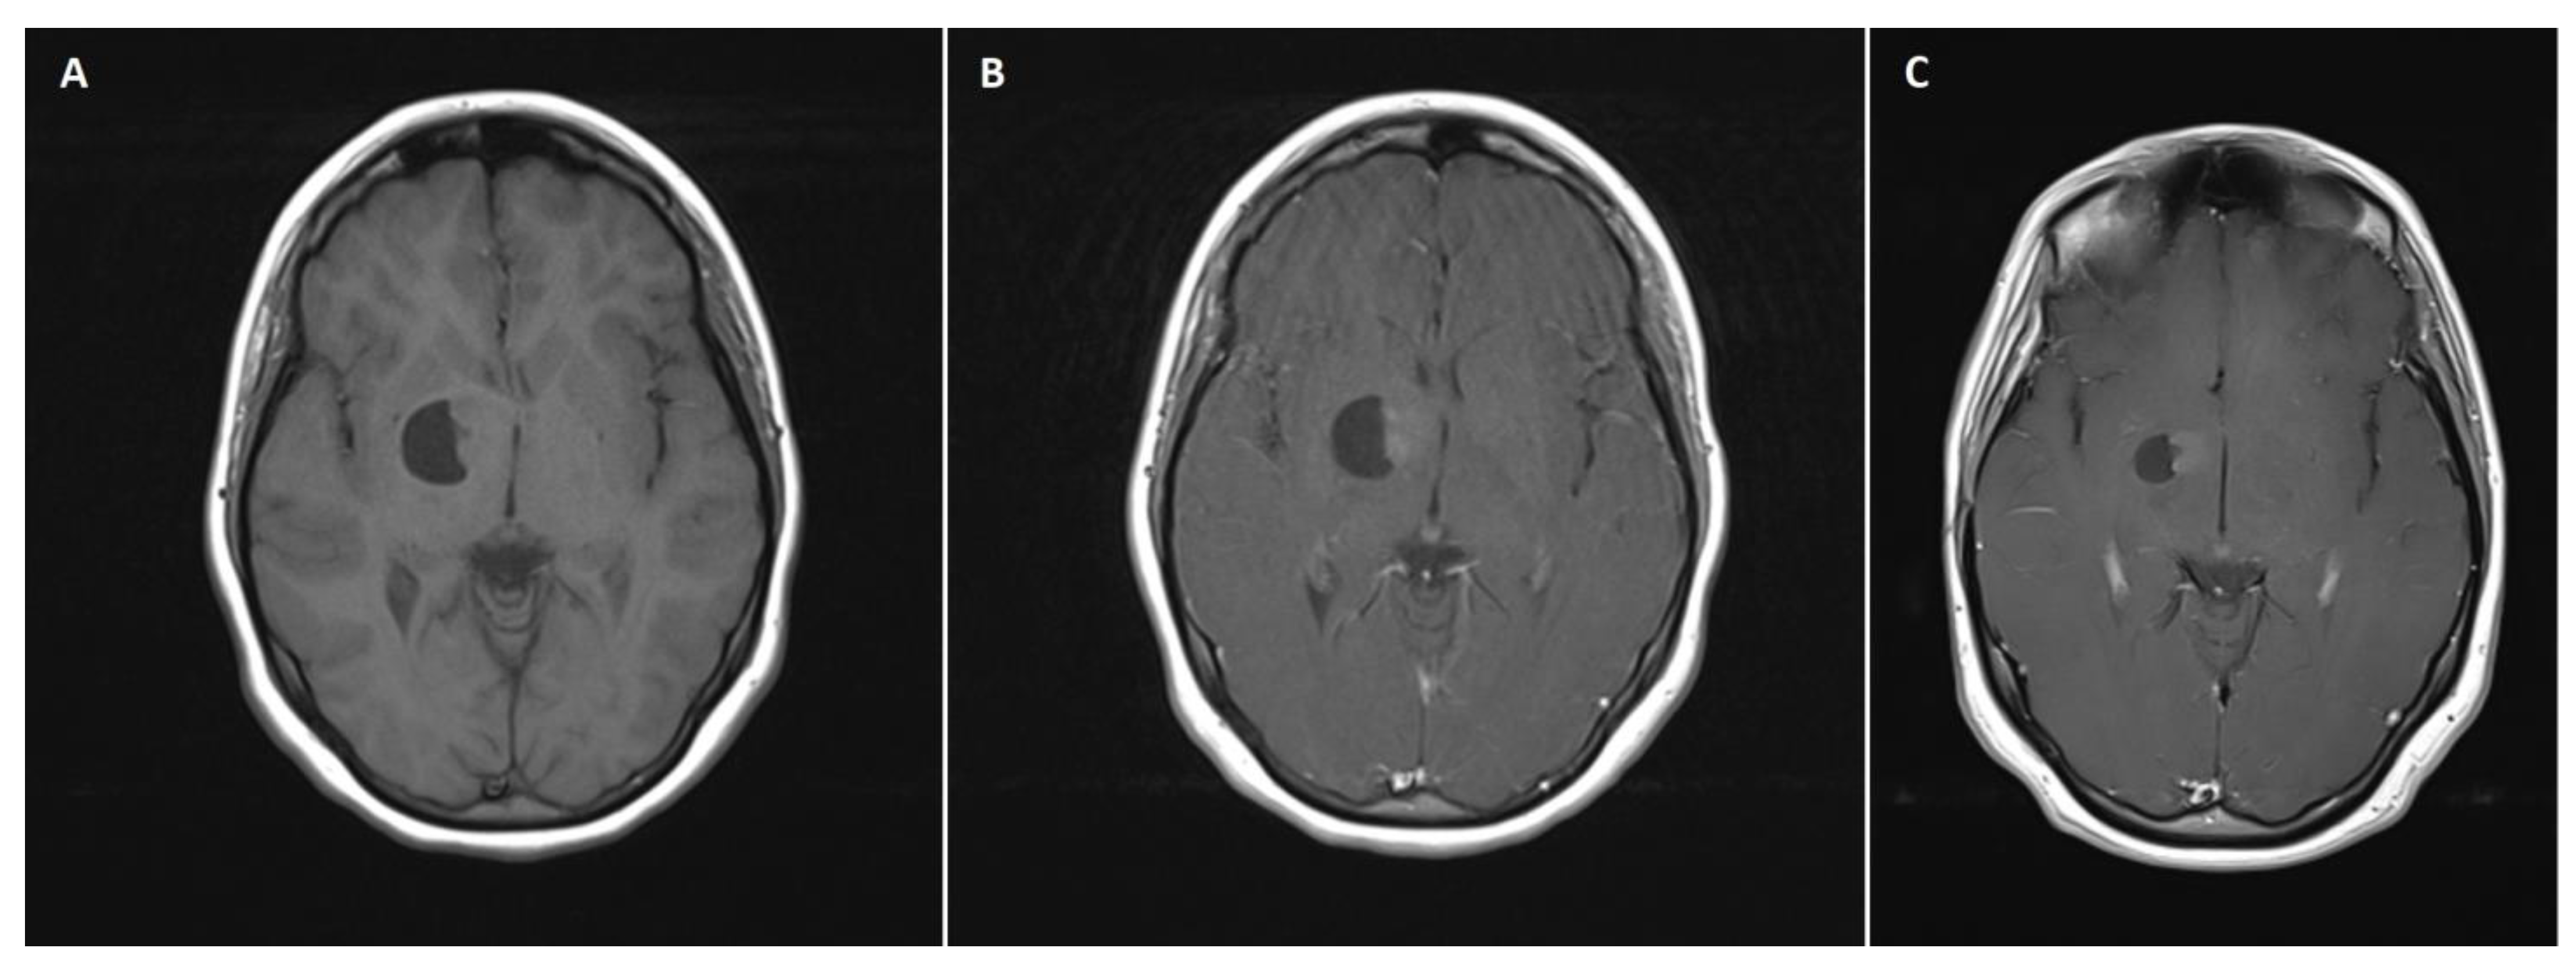

A 14-year-old female patient with recently diagnosed pertussis underwent a CT scan of her paranasal sinuses. Imaging data revealed a left-sided space-occupying lesion at the level of the thalamus. The patient underwent a subsequent brain MRI scan, which showed a cystic–solid 3 cm × 2.5 cm mass located within the anterior thalamus and basal ganglia on the left side (Figure 1A,B). On admission, the patient was neurologically intact. Due to the mass effect exerted by the tumor, the patient qualified for surgical tumor removal. Considering the eloquent location of the adjacent neural tissue, GTR was not achieved to preserve neurological function postoperatively. No surgery-related complications occurred. A postoperative MRI scan confirmed subtotal resection of the tumor (Figure 1C). The patient was discharged home without any neurological deficits. Subsequent pathological examination revealed ganglioglioma (WHO grade 1 tumor). The patient has been followed up for 111 months, with neither radiological regrowth nor the occurrence of focal neurological symptoms. However, the patient complained of periodic headaches, which are unlikely to be caused by the surgery.

Figure 1. A 14-year-old girl with right-sided thalamic ganglioglioma. (A) A preoperative axial non-contrast T1 MRI scan showing an isodose solid mass located within the right thalamus with an adherent cystic component, causing a mass effect and slight midline shift. (B) The preoperative axial postcontrast T1 MRI scan revealed a heterogeneous solid mass enhancement. (C) A postoperative axial postcontrast T1 MRI scan reflecting subtotal excision of the tumor, with reduced size of the cystic component, relieved mass effect, and no evident midline shift.